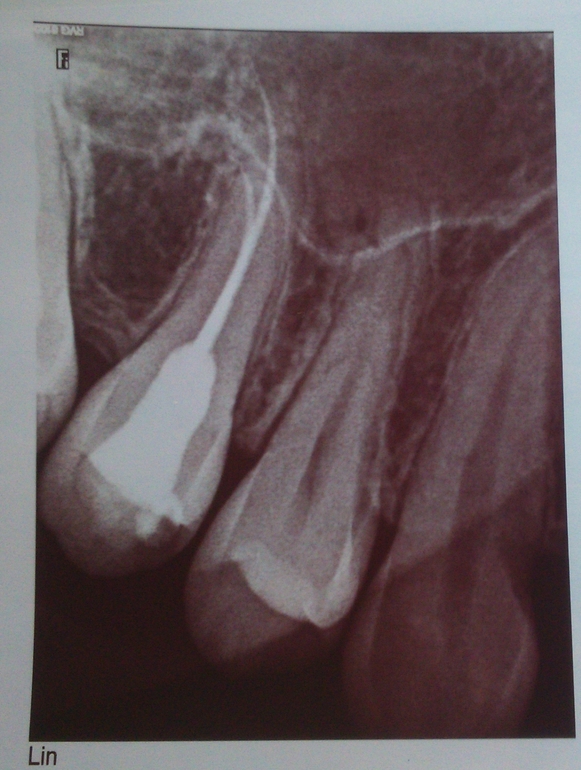

Здравствуйте! У меня такая непростая ситуация. удалили 1и 2 зуб, через месяц стало больно нажимать на клык, думала пройдёт,, с виду зуб полностью здоровый, пару раз отправляли домой. Но однажды стали стреляющие боли нестерпимые боли. В стоматологии сделали снимок, не могли понять в чём именно дело, остановились на клыке. Так как я беременна, мне его тут же предложили удалить, мол не ковыряться. Но боли так и остались. Снимки прикрепляю. Можете подсказать, может на снимке видно, может мне убрали не тот зуб.....???????????????